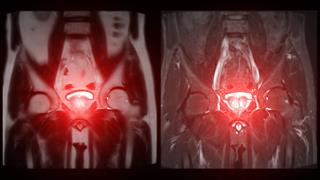

Διαδερμικά επιθέματα οιστραδιόλης στον τοπικά προχωρημένο καρκίνο του προστάτη

Νέα δεδομένα αλλάζουν τον σχεδιασμό θεραπείας στον καρκίνο του προστάτη

Εξέταση PSA για τον προστάτη: Εξίσου αξιόπιστη με τη μαστογραφία (μελέτη)

Καρκίνος προστάτη: Ορμονοθεραπεία στη μετεγχειρητική ακτινοθεραπεία - Ποιοι ασθενείς ωφελούνται

Ριζική προστατεκτομή: Ακτινοθεραπεία καθοδηγούμενη από PSMA PET/CT [μελέτη]

Καρκίνος του προστάτη: Νέο μοντέλο πρόβλεψης κινδύνου θανάτου μετά από PSA

Πόσο πρέπει να διαρκεί ο ανδρογονικός αποκλεισμός στον εντοπισμένο καρκίνο του προστάτη

Νέα θεραπευτική αγωγή για τον καρκίνο του προστάτη [μελέτη]